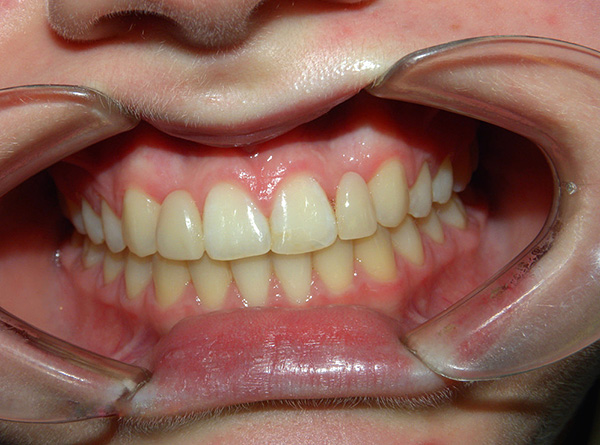

- Morso ortognatico - è considerato il più estetico e più favorevole per mantenere uno stato sano dei tessuti molli della cavità orale e delle articolazioni temporo-mandibolari. Il morso ortognatico ha le seguenti caratteristiche: i denti nella parte laterale sono chiusi secondo la classe I di Engle, vale a dire, il tubercolo anteriore-buccale della "sei" superiore si trova nella fossa inter-tubercolare del 6o dente inferiore. I denti anteriori della mascella superiore si sovrappongono agli incisivi della mascella inferiore di non più di un terzo.Tutti i denti su entrambe le mascelle sono in stretto contatto tra loro. Inoltre, hanno una certa pendenza, garantendo la loro posizione regolare e corretta;